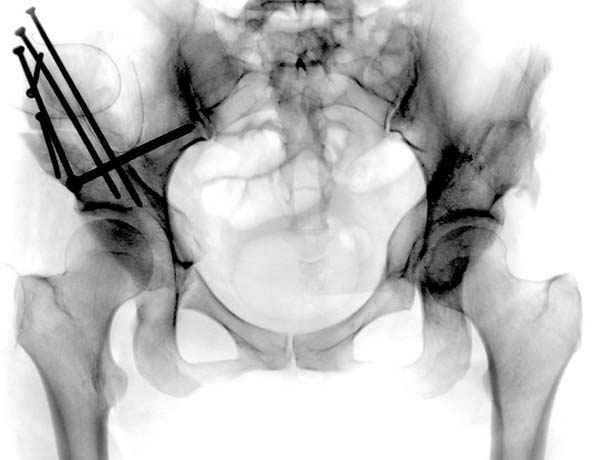

Рис.2 Та же трехмерная модель тазобедренного сустава без аналога связки головки бедра. Пружина динамометра удерживает тазовую часть модели от опрокидывания, поддерживая стабильность так же, как отводящие мышцы обеспечивают ее в отсутствии связки головки бедра.